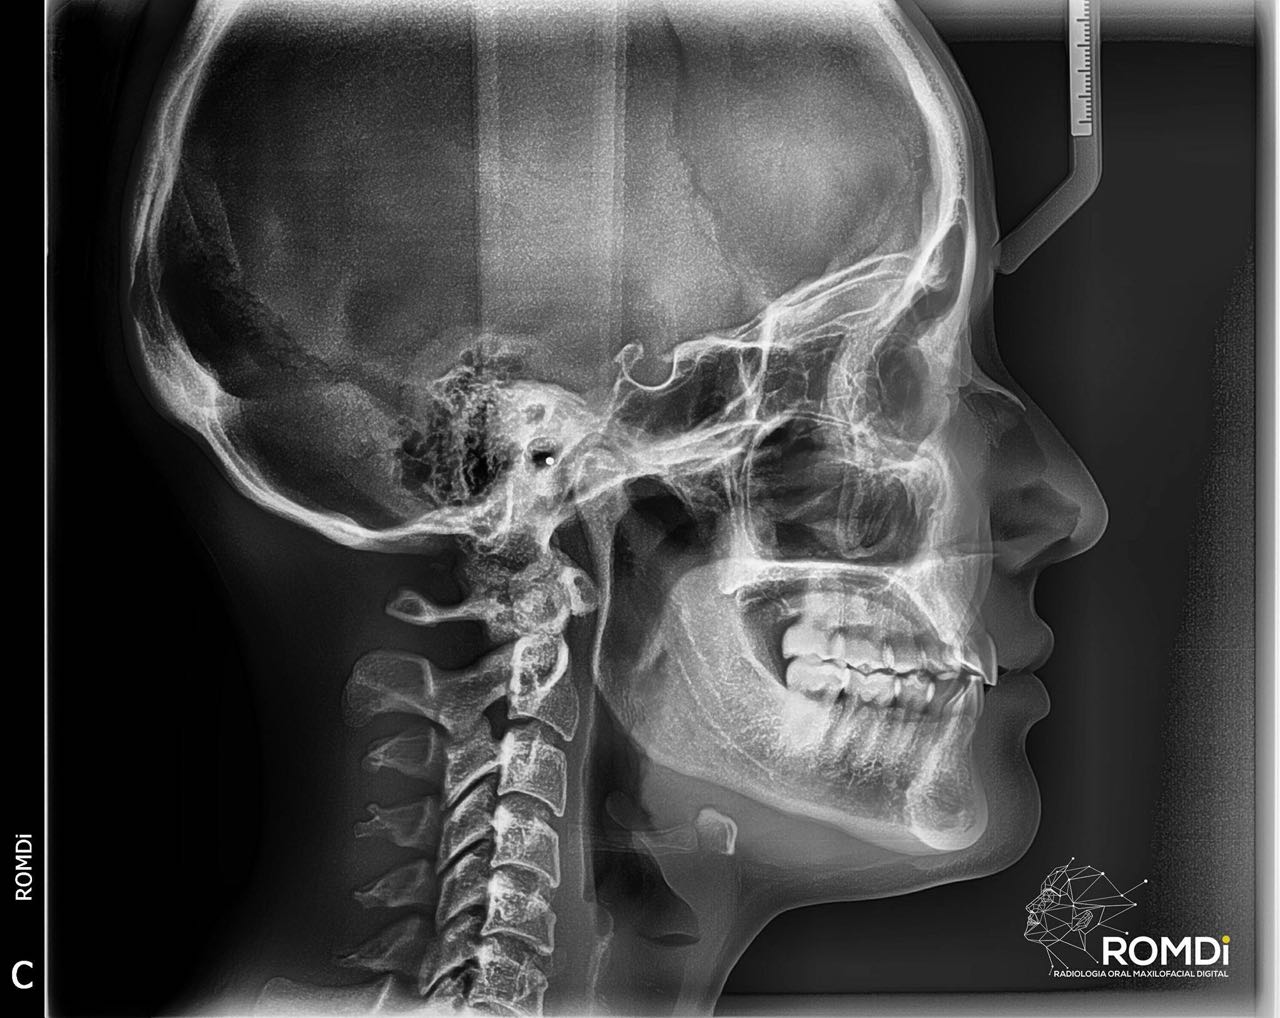

A través de la radiología, se conocen diferentes sistemas auxiliares de diagnóstico especializados de exploración, que nos proporcionan una información que ningún otro método nos puede ofrecer, tomando en consideración los avances técnico y científicos. En la materia de radiología, la actualización y aplicación de estos nuevos métodos, son necesarios para poder obtener el conocimiento básico y avanzado en el manejo de la interpretación radiográfica, así mismo, en conjunto con otros estudios clínicos, poder tener un diagnóstico acertado en las radiografías.

Nuestro equipo radiológico es de primera generación, con lo que podemos brindar a nuestro clientes imágenes médicas de alta calidad de manera rápida, ademas de contar con un servicio web que permite la distribución y almacenamiento digital en la nube.